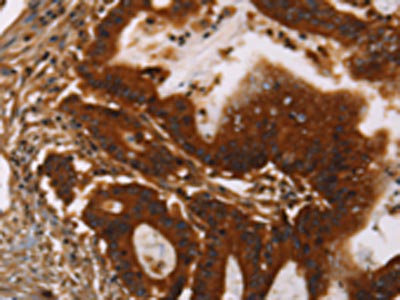

IHC (Immunohistochemistry)

(The image on the left is immunohistochemistry of paraffin-embedded Human colon cancer tissue using AAA237437(GPA33 Antibody) at dilution 1/30, on the right is treated with fusion protein. (Original magnification: ×200))